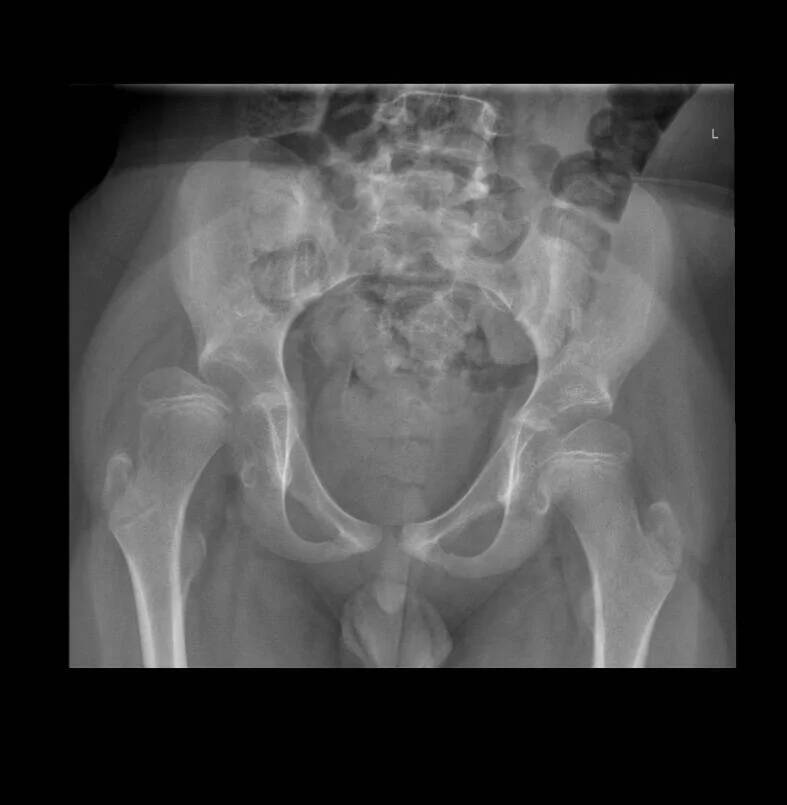

Ieder half jaar wordt er een heupfoto gemaakt.

Op de foto zien ze hoeveel procent beide heupen uit de kom staan.

Jayden moest echt geopeerd gaan worden, want zijn rechterheup staat 60% uit de kom.

De heupen bestaan uit een kop en een kom die precies in elkaar passen.

Vanwege Jayden zijn handicap loopt Jayden niet zoals wij, hierdoor is de kop en kom nooit mooi ingeslepen.

Daardoor glijdt de kop er bijna uit en staat deze recht en niet scheef zoals bij ons.

Om dit weer mooi aan te laten sluiten gaan ze zijn kom verlengen, zijn kop opvullen met heupbot zodat het weer rond word en kop en kom weer mooi in elkaar passen.